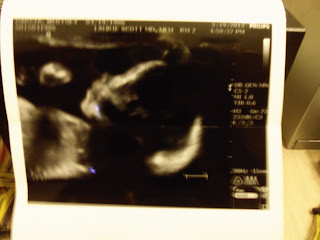

Today we went to the perinatologist for my LAST visit with them! yaaaaay! No more co-pays for them! They said Baby G is perfect! They also said he is very active and seems very healthy and happy. He was boxing with my stomach during the ultrasound and sticking his tongue out and playing peek-a-boo, how does he know we are watching him?? He is a goof ball! I loved seeing what I was feeling because I always wonder what the heck he is up to.

He is opening his mouth, maybe yawning??